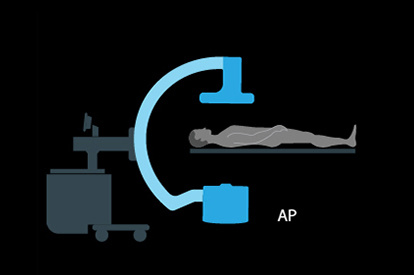

The ANGIO Mentor simulator is an essential tool for clinicians to practice and acquire the skills needed for performing endovascular interventions. Trusted by medical associations, hospitals, training centers, and the medical device industry globally, it provides trainees with realistic clinical settings to practice endovascular interventions using fluoroscopic and ultrasound guidance.

Offers true-to-life simulation of the clinical environment, including advanced imaging modalities like fluoroscopy/echocardiography, hemodynamic monitoring, medications, and interventional devices

C-arm Basic Skills Module